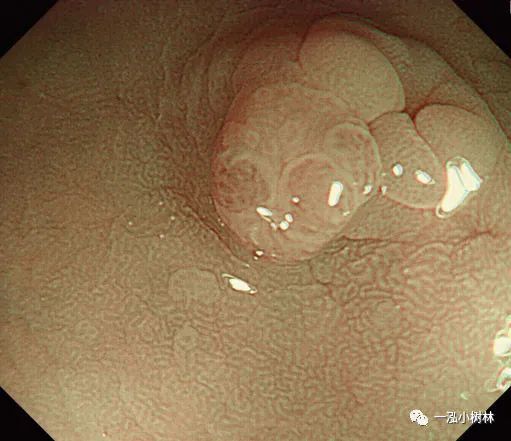

例5 小息肉冷圈套切除术

图片

图5a 横结肠处4mm大小0-IIa型腺瘤

图5b 在病灶上方圈套

图5c 圈套包括病灶周围1-2mm正常黏膜

图5d 对病变进行机械性横切

图5e 对病变进行机械性横切

图5f 息肉取出后出血

图5g 黏膜出血止血

图5h 可见息肉边缘正常黏膜的标本